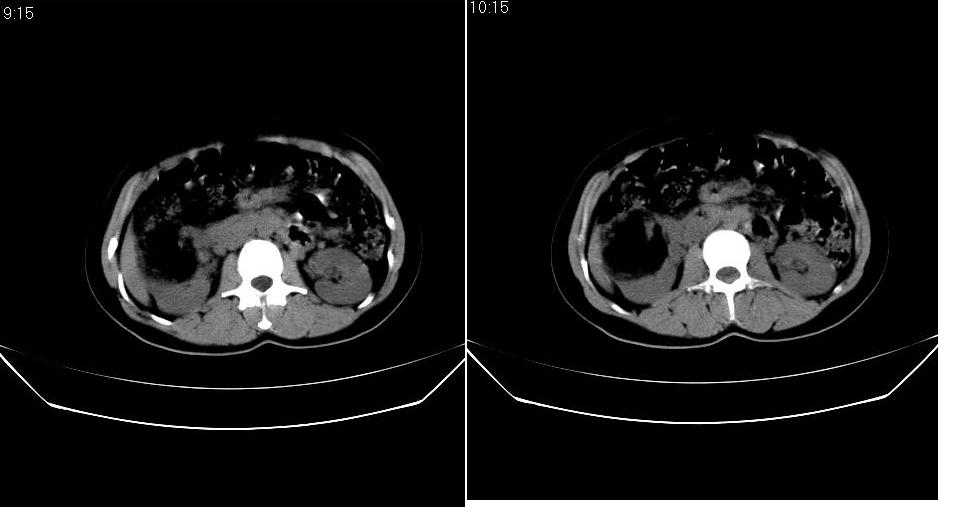

以下是引用求知若渴在2007-9-10 20:08:00的发言:[br]病变以脂肪成分为主,应该是错构瘤。另肝内胆管结石

以下是引用xulianj在2007-9-10 20:51:00的发言:[br]错构瘤,支持。含脂肪成分较多,证明较为成熟。

以下是引用王仕学在2007-9-10 21:34:00的发言:[br]有脂肪密度,哪怕是一点点,首先考虑错构瘤。还是增强吧,好说些!